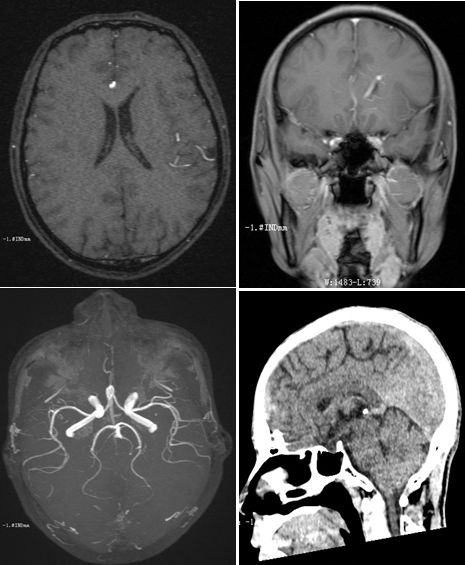

病例6

男性,67岁,因言语不清、走路不稳1天入院。既往有脑梗死和糖尿病病史,不规律服用二甲双胍,血糖控制欠佳。查体:不完全运动性失语,左侧鼻唇沟浅,口角右歪,伸舌稍偏左。余查体阴性。

增强MRI如下:

答案:肺癌脑转移

患者老年男性,多个卒中危险因素,出现卒中样症状。头MRI可见右侧桥脑小脑角区病变,DWI未见高信号,增强显示软脑膜强化,高度提示感染和肿瘤。好多老师考虑CLIPPERS,CLIPPERS多是双侧病灶,患者病灶分布于中脑、小脑及丘脑,增强表现为脑桥血管周围呈“胡椒粉”样斑点状强化病灶,部分强化病灶以脑桥为中心,随着距脑桥距离的增加,相邻病灶的数量逐渐减少,范围也逐渐缩小。